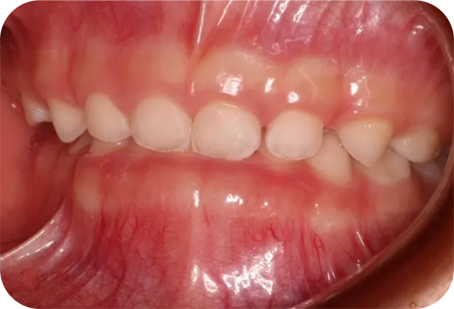

ムーシールドは受け口(反対咬合)を改善する装置です。(受け口とは下の前歯が上の前歯より前に出ている噛み合わせの事です)

主に就寝時に専用マウスピースをつける事で、舌や口腔周囲筋の状態を整え、反対咬合を改善します。

4歳から可能で、特に乳歯列期に治療を行うと、正常な顎骨の成長発育を促すことができるため、正しい永久歯の成長も期待できます。

咬み合わせが逆のまま成長すると、下顎の骨が過成長しやすい状態が続き、結果取り返しのつかないほど大きくなってしまう事もあるため、本人の負担軽減のためにも咬み合わせは早期に治しましょう。